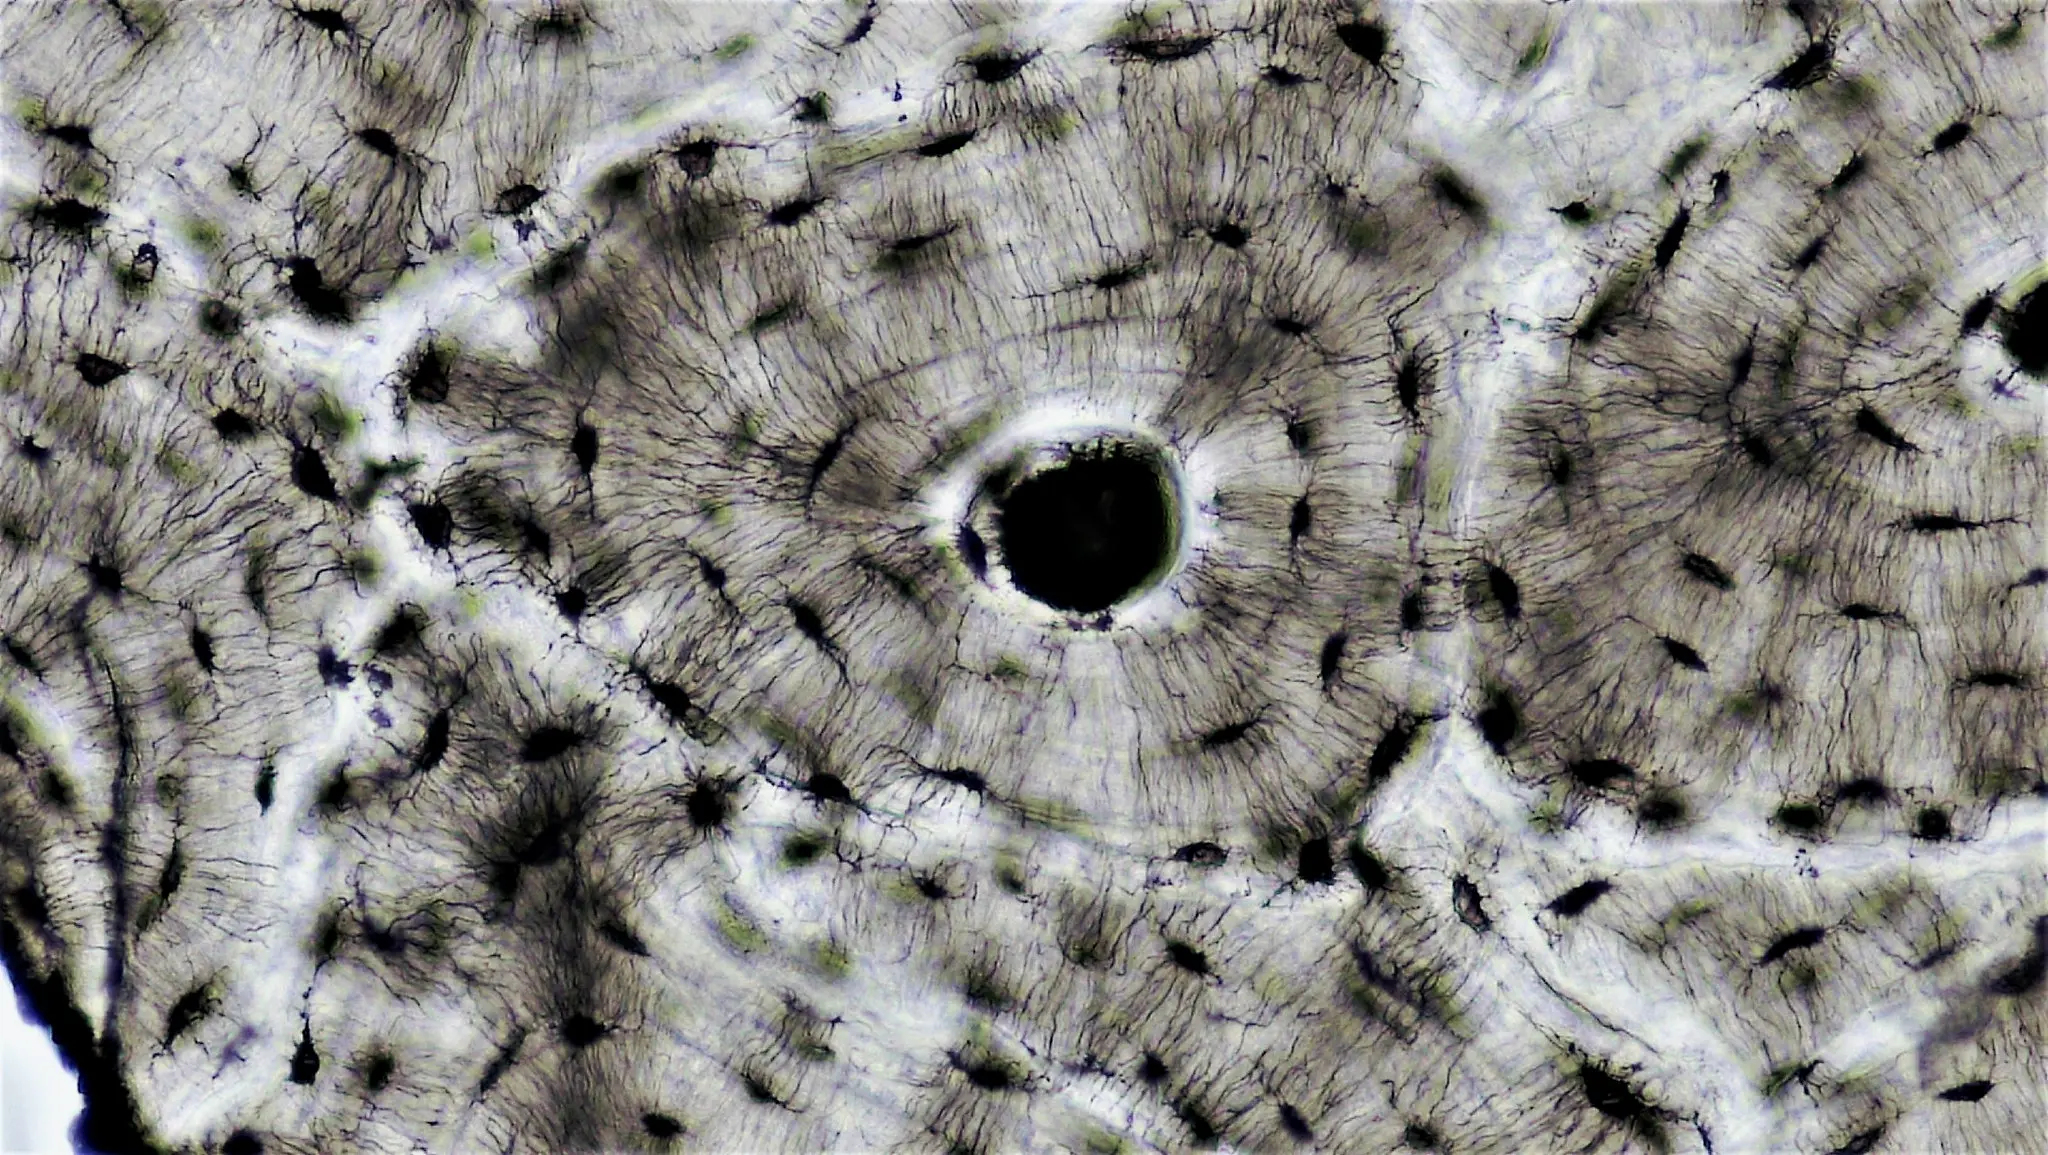

Canale di Havers e canali di Volkmann: anatomia dell'osteone, struttura dell'osso corticale e ruolo nella vascolarizzazione ossea.

Canali di Havers e Volkmann, sistema haversiano e rete capillare. Anatomia interattiva e ruolo del microcircolo in implantologia.

Il connettoma degli osteociti: nuova frontiera per comprendere la salute ossea e sviluppare terapie innovative.